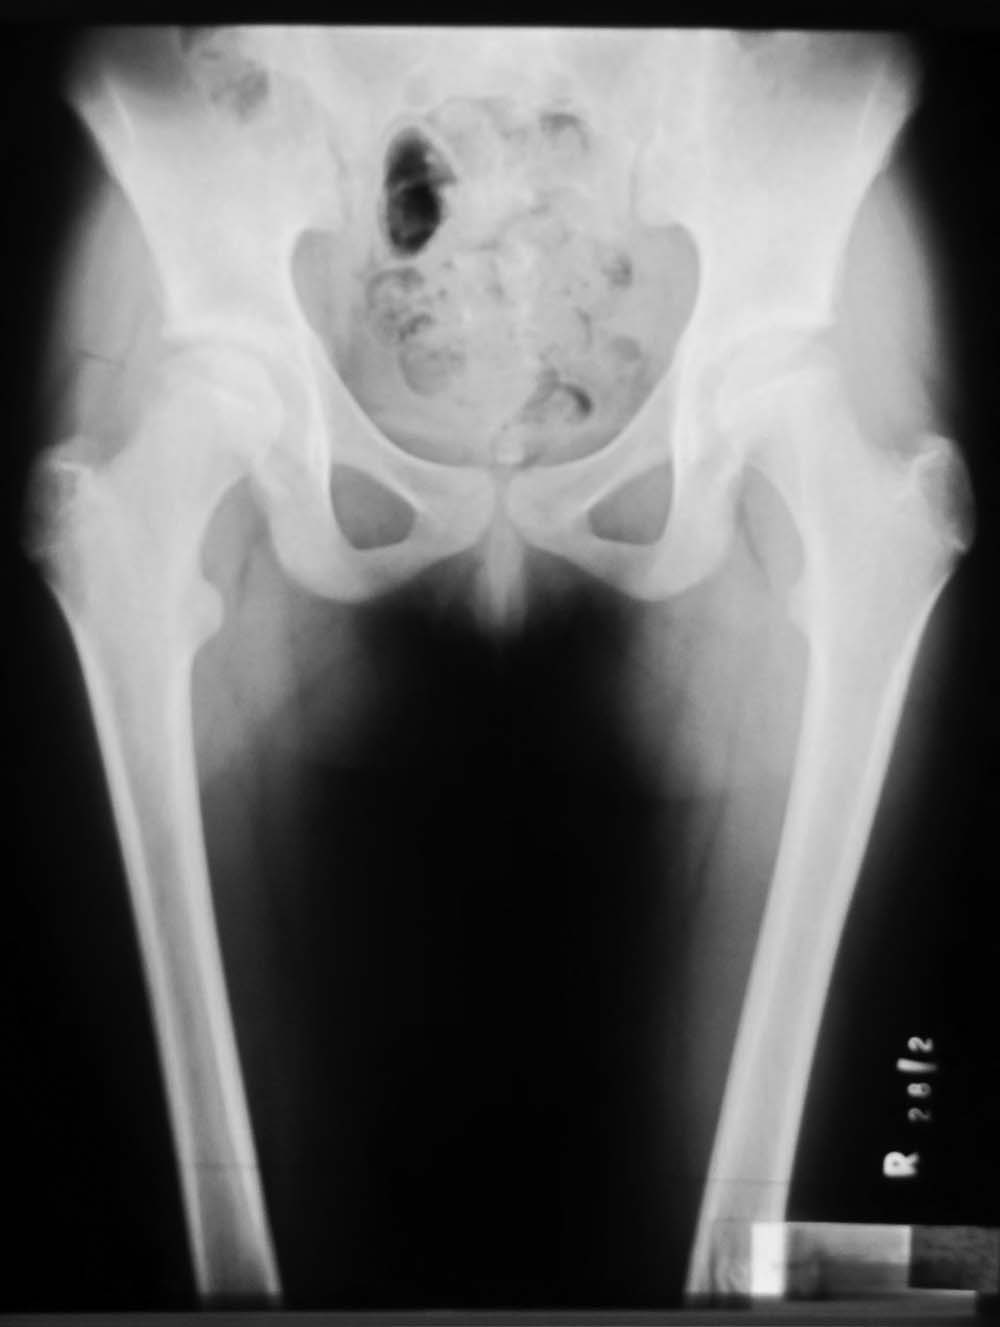

Обратилась пациентка 12 лет, 7 месецев назад стали замечать хромоту.

Лечилась консервативно. Снимки в приложении. Выражена хромота, резко ограничены отведение и ротационные движения бедра. Чем можно помочь сейчас или "поезд ушел"? Прогноз? Буду блогодарен любым соображениям.

Аршак! Сделай КТ, лучше трехмерку. Дальше будем решать. Процесс по восстановлению эпифиза завершился, но с явной деформацией. АИФ

У меня более взрослые больные с последствиями и поэтому вопрос к педиатрам-специалистам по заболеванию Пертес. Не вызывает ли сомнения диагноз? Меня смущает небольшой срок истории и возраст пациентки. Болезнь может встречаться до 12 летнего возраста, но к этому времени у многих заканчиваются все стадии развития заболевания, включая вовлечение в процесс ацетабулума. Обычно процесс течение заболевания немного дольше, чем "7 месецев назад стали замечать хромоту".

Встречается ли заболевание без характерного склероза с молниеносным течением в 12 летнем возрасте? По-моему, изчезновение головки в короткий срок характерно для септических состояний, и поэтому на первое место в дифференциальной диагностике я бы поставил на септический артрит? Заново собрать анамнез на восспалительный процесс, анализы, пункция?

Доисследование покажет, что от чего, но это не сохранит головку бедра. Лечение состоит в ограничении нагрузки с периориентацией головки. От подвывиха головки сохранит варусная остеотомия, и в дальнейшем создаст опору. После операции движение в суставе на Continuous passive motion.

In this age prognosis is bad , but I think that she will improve after Vagus osteotomy -the goal is to remove necrotic part of the head from the weight bearing edge of the acetabulum